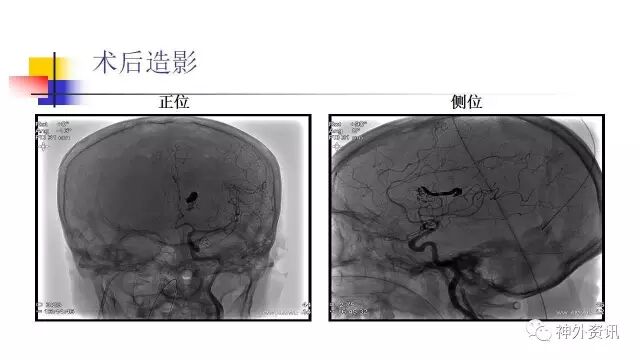

手术过程